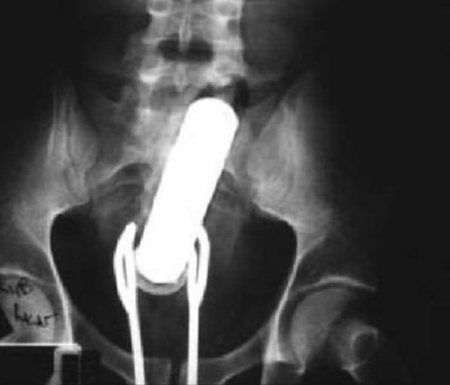

お尻は日本でもたまーに救急に来るで

肛門 異物

肛門に異物はよくあるらしい。やり過ぎると地主になってしまうので程ほどにね。

尻に異物が入る時はだいたい「転んだ拍子に」って言うけど医療関係者はそんな与太話は誰も信じてないだろうね。